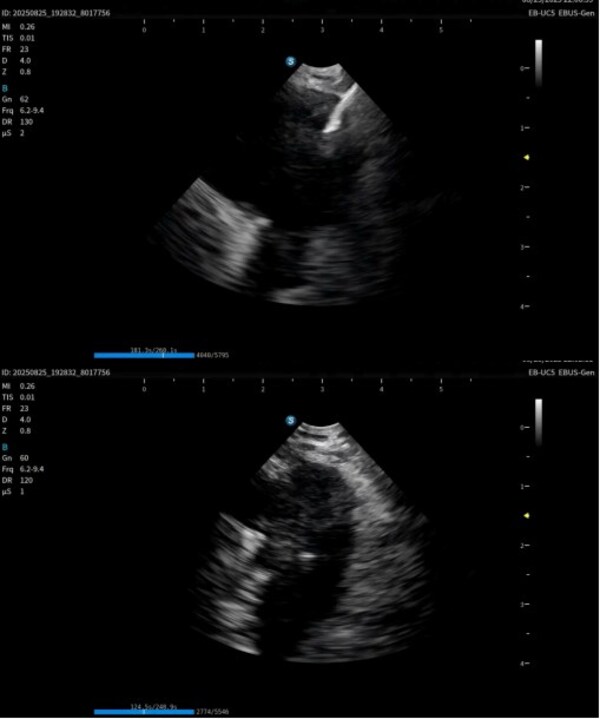

作為在呼吸診療領(lǐng)域的重磅產(chǎn)品,本次在產(chǎn)品創(chuàng)新設(shè)計(jì)上和工藝技術(shù)上取得了重大突破,顯著提升了光學(xué)圖像和超聲圖像的質(zhì)量,同時(shí)鏡體保持了良好的操作性,在鉗鏡比和視野角綜合參數(shù)可達(dá)到全球同類產(chǎn)品最佳性能。目前在臨床應(yīng)用表現(xiàn)突出,取得了專家的認(rèn)可和好評(píng)。

超聲電子支氣管內(nèi)窺鏡憑借其"微創(chuàng)、精準(zhǔn)、安全"的特點(diǎn),已成為呼吸介入領(lǐng)域的核心技術(shù)之一。開立醫(yī)療全系列產(chǎn)品全面上市可為肺部腫瘤、縱隔病變提供管內(nèi)清晰光學(xué)影像,管外高清聲學(xué)斷層組織及血流影像,提供精準(zhǔn)可視化介入操作,為疾病的診斷提供更精準(zhǔn)、更安全、更高效的一體化診療解決方案。